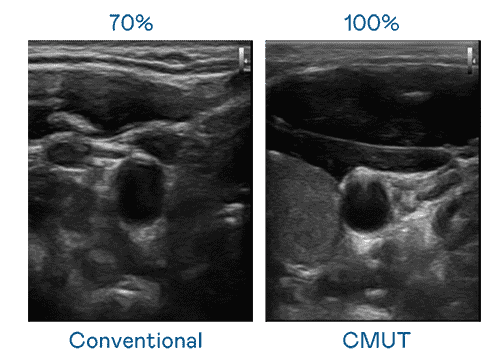

CMUT 技术是一种用电容式微机电元件来产生超音波讯号的技术。。与传统 PZT 压电式技术相比,,,,CMUT 频宽增加 30%,,,,更宽频的超音波讯号让影像解析度大幅提升,,是实现高影像品质医疗超音波扫描、、、、促进精准医疗发展的关键技术。。。

大频宽带来超清晰影像

超音波影像的解析度高低,,,,首先取决于探头能发出的讯号频宽。。。。2468BET CMUT 可提供高清晰的超音波讯号,,提供高频宽、、、、高灵敏度、、影像纹理细节更高的超音波影像,,协助医护人员缩短影像判读时间及利用精准的医疗影像进行诊断。。。